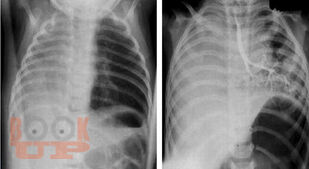

В предлагаемом учебном пособии представлены вопросы эмбриогенеза, классификации, диагностики и способов современного хирургическоголечения некоторых врожденных аномалий лёгких у детей. Учебное пособие соответствует образовательной программе ФГОС ВО 3+ для студентов медицинских вузов, обучающихся по специальностям «Лечебное дело»,«Педиатрия». Учебное пособие предназначено для освоения компетенций ОК-4, ОК-5, ОПК-10, ПК-5, дисциплины «Общая хирургия, хирургические болезни» стоматологического факультета, компетенций ПК-5, ПК-6, ПК-22 дисциплины «Детская хирургия» педиатрического факультета, компетенций ПК-14, ПК-17, ПК-26 дисциплины «Госпитальная хирургия, детская хирургия» лечебного факультета.